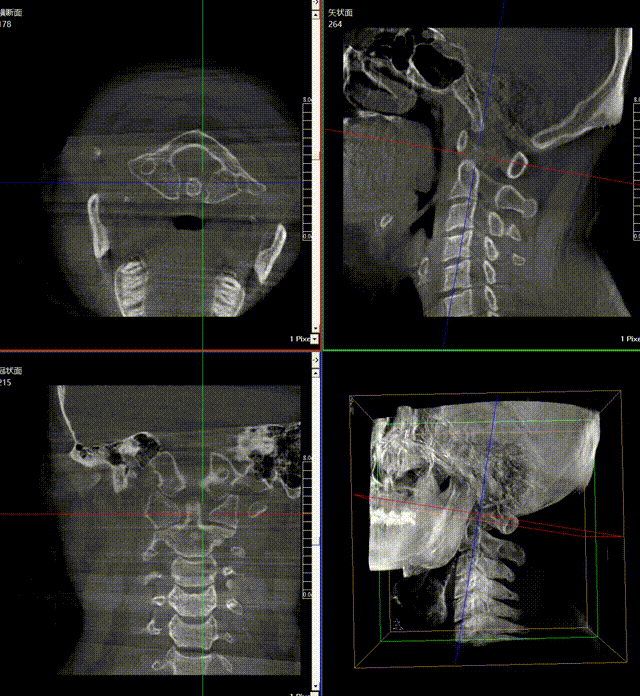

通常上頸椎的手術(shù)是非常復(fù)雜的,因?yàn)獒t(yī)生要把釘子打在上頸椎這樣一個(gè)很狹小的通道里面,周?chē)际侵匾纳窠?jīng)血管,一旦損傷到頸椎,就有可能造成病人的死亡。隨著醫(yī)學(xué)影像技術(shù)的不斷發(fā)展,在三維影像的引導(dǎo)下,整個(gè)打進(jìn)去的通路能夠完全的展現(xiàn)在我們的眼睛里,讓這種復(fù)雜的手術(shù)變得簡(jiǎn)單了,更多的醫(yī)生就可以去開(kāi)展這樣的手術(shù)了,也會(huì)有越來(lái)越多的病人從中獲益。